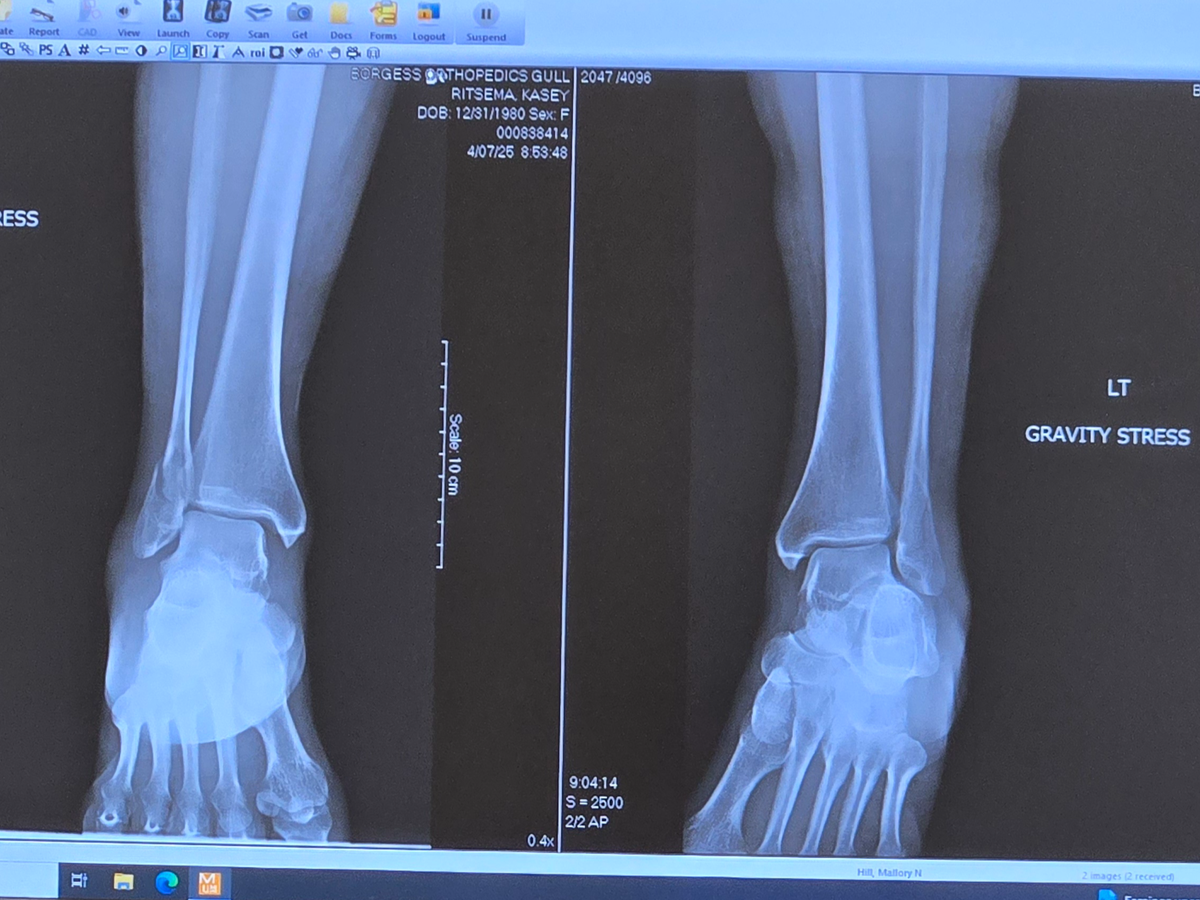

Hi everyone. My name is Kasey Ritsema. On Monday, March 31st, 2025, I had an unbelievable accident. I fell and broke both of my ankles and sprained my left knee. I went to see my orthopedic surgeon yesterday morning, April 7th, 2025. I was told my options were to have surgery to fix them or not. If I chose not to go through with the surgery, when I started to walk again on my own without the support of the orthopedic boots, every step that I took was going to feel as if I was about to fall because of the way they would heal. I definitely don't think that would be a very good quality of life, constantly feeling as if I were going to fall. As much as I was hoping to avoid surgery, I agreed to have the surgery done. They are putting plates and screws in my leg to fix my ankles on Wednesday, April 9th, 2025.